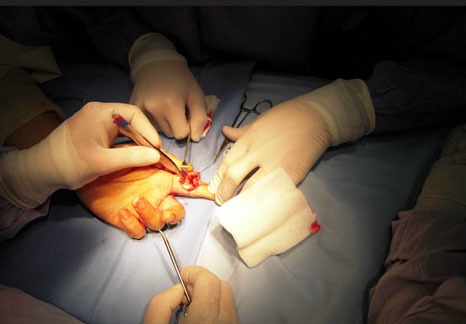

CIRUGIA DE MANO

Y MIEMBRO

SUPERIOR

Casos de exito

Cirugías, operaciones y tratamientos.

ESPECIALISTA EN ORTOPEDIA Y

TRAUMOTOLOGIA,CIRUGIA DE MANO

Y MIEMBRO SUPERIOR